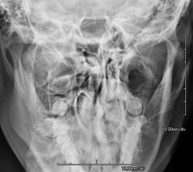

- TMJ X-ray (Temporomandibular Joint)

This technique uses X-ray rendered imaging for examining the temporomandibular joint. Indicated for: trauma, chewing pain, chewing noise, limited mouth opening.